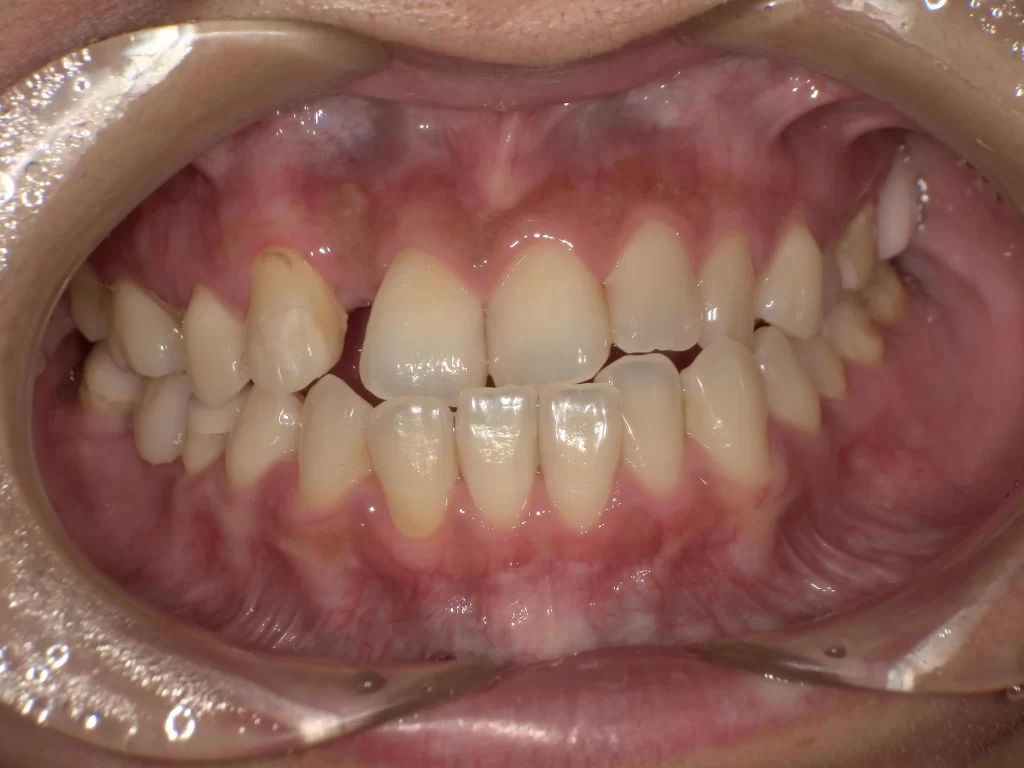

症例⑤:10歳・ガタガタ・出っ歯・深い噛み合わせ

【使用期間:3ヶ月】

歯が生えるスペースが足りずガタガタしており、噛み合わせも深い状態でした。

▼ 治療前(Before)

▼ 使用3ヶ月後(After)

- 年齢・症状: 10歳、叢生(ガタガタ)、過蓋咬合

- 治療法: プレオルソ

- 期間: 3ヶ月

- 結果: 装置を使うことで歯列の横幅が拡大し、ガタつきが自然に改善されました。深い噛み合わせも良くなっています。